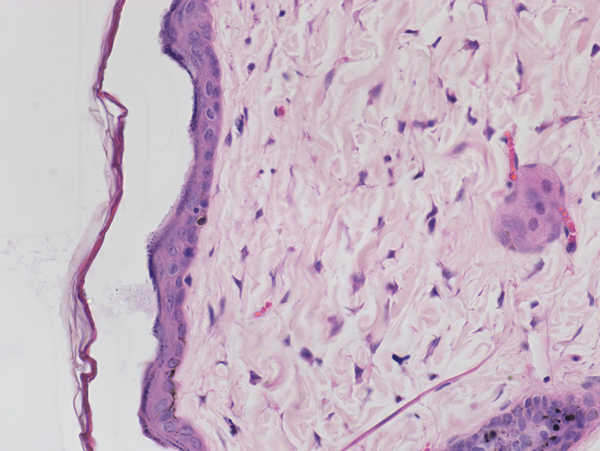

生物显微镜下的HE染色病理切片

病理切片经过HE染色法选择性地染色,由于组织或细胞的不同成分对苏木精和伊红的亲和力不同及染色性质不一样,经染色处理后细胞核及钙盐粘液等呈蓝色,细胞胞浆呈粉红色,通过生物显微镜,可观察到各种组织或细胞成分与病变的一般形态结构特点。

生物显微镜ML31采用无限远光学,平场消色差物镜和10X/22mm大视野目镜,观察HE染色病理切片真实清晰,搭配病理诊断上深度优化的显微相机MS60,采集的图像锐利、色彩还原准确,为临床诊断和治疗提供的优秀图像数据。